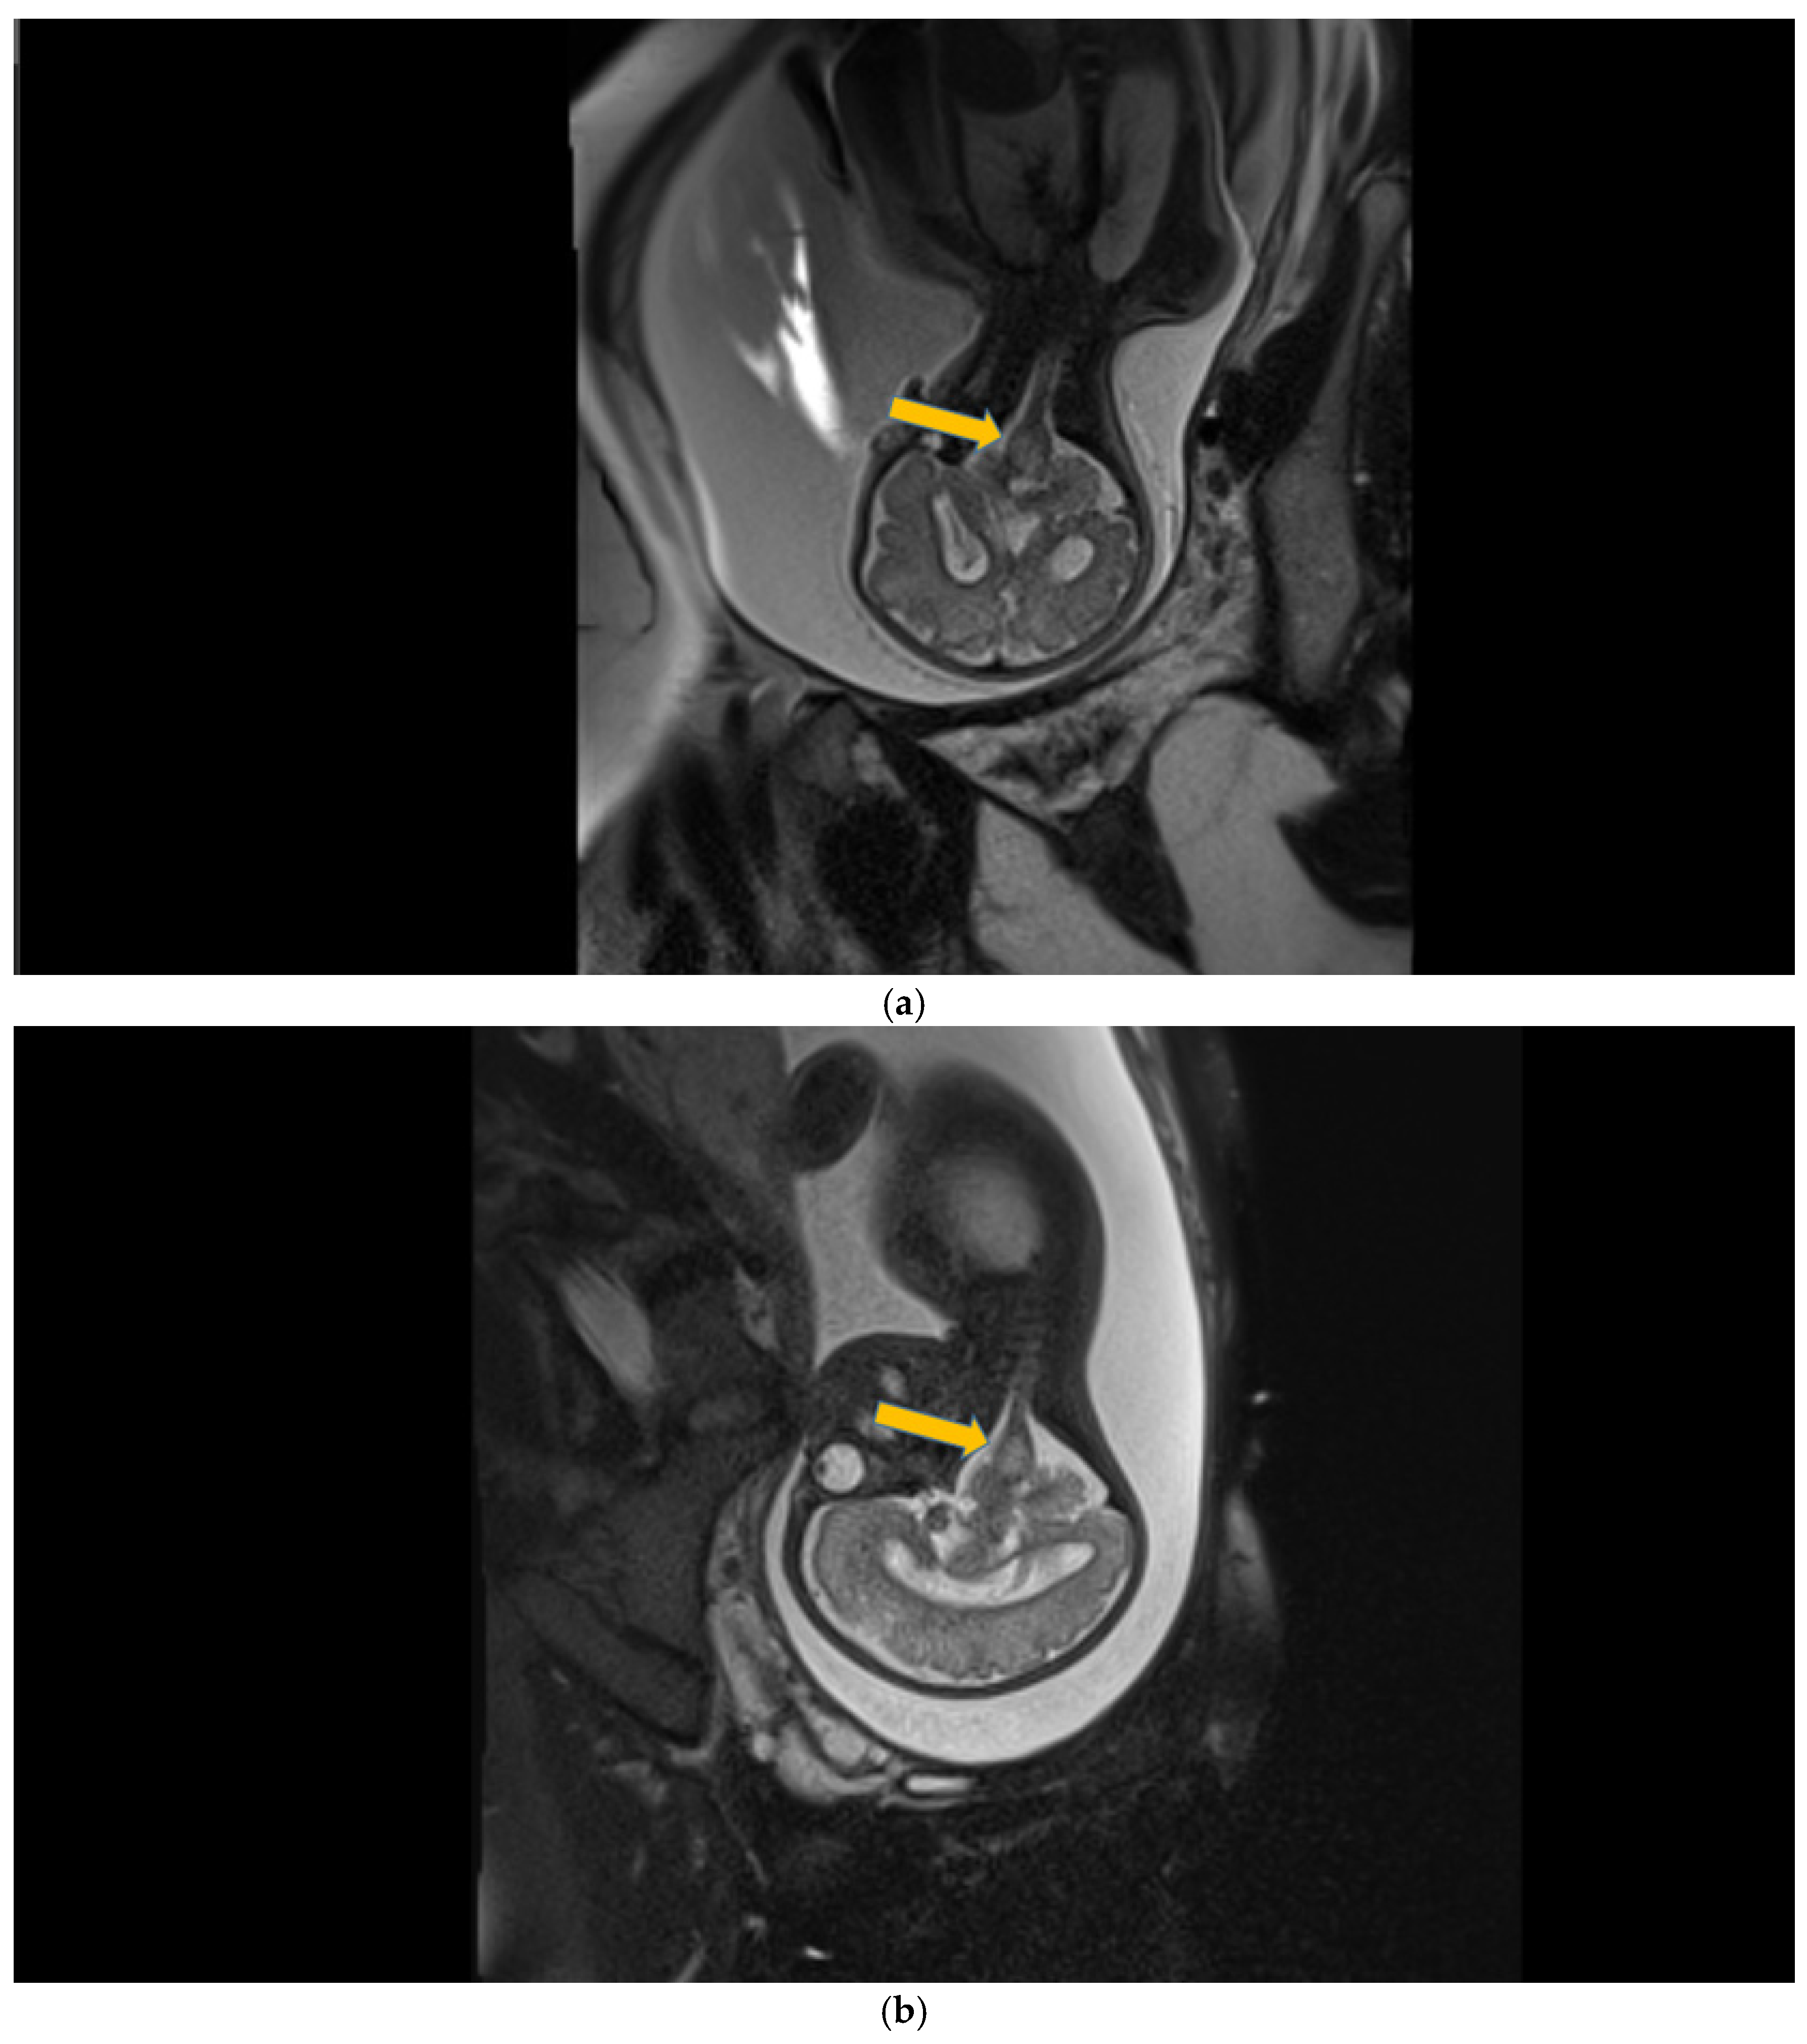

Case 3 involved a preterm newborn (33 3/7 weeks of gestation) with antenatal lateral ventricle asymmetry, for which a left ventricular hyperechoic image with the fetal MRI was performed at 28 weeks of gestation, born from a mother with recurrent UTIs (urinary tract infections) with E. Coli who was extracted through C-section and required resuscitation at birth (T-piece resuscitator). A nasal CPAP was provided for almost 36 h and antibiotic therapy was initiated (Vancomycin® and Cefotaxime® for three days).

The first CUS was performed 24 h after birth and showed dilation of the third and fourth lateral ventricles, enlargement of the Sylvius aqueduct, and the presence of an arachnoid cyst (Figure 3a–e).

Figure 3.

(a) Cranial ultrasound. Coronal view. Enlargement of the lateral ventricles with hyperechoic and third ventricle dilation. D1, D2—Levine index measurement. D3, D4—anterior horn width measurement. D5—third ventricle (personal image collection). (b) Cranial ultrasound. Sagittal view. Up—left ventricle. D1, D2—lateral ventricle measurements and thalamo-occipital horn width. Down—right ventricle. D1, D2—lateral ventricle measurements and thalamo-occipital horn width (personal image collection). (c) Cranial ultrasound. Sagittal view. Up—enlargement of the third and fourth ventricles. Measurements of the ventricles. Down—measurement of the resistive index (RI) performed on the anterior cerebral artery (ACA) using Doppler flow measurements. RI—0.74 (personal image collection). (d) Cranial ultrasound. Transtemporal view. Yellow arrow—enlargement of the Sylvian aqueduct (personal image collection). (e) Cranial ultrasound. Sagittal view. Yellow arrow—arachnoid cyst posterior to the third ventricle (personal image collection). (f) Cranial ultrasound. Coronal view. Lateral ventricles and third ventricle enlargement. D1, D2—Levine index measurement. D3, D6—right lateral ventricle measurement (anterior horn width). D4, D5—left lateral ventricle measurement (anterior horn width) (personal image collection). (g) Cranial ultrasound. Sagittal view. Left—left ventricle. D1—thalamo-occipital distance measurement. Right—right ventricle. D2—thalamo-occipital distance measurement (personal image collection). (h) Cranial ultrasound. Coronal view. Up—orange arrow—third ventricle. Red arrow—fourth ventricles. Yellow arrow—arachnoid cyst. Down—resistive index measured on the anterior cerebral artery. RI—0.79 (personal image collection). (i) Cranial ultrasound. Transversal view. Up—RI precompression value on the middle cerebral artery performed with Doppler examination. RI—68. Down—RI post-compression value on the middle cerebral artery performed with Doppler examination. RI—0.79 (personal image collection). (j) Cranial ultrasound. Up—coronal view. L1, L2—Levine index measurement of the lateral ventricles. Down—sagittal view. L1, L2—measurement of the thalamo-occipital distance (personal image collection). (k) Cranial ultrasound. Sagittal view. L1, L2—measurement of the third ventricle. L3, L4—measurement of the fourth ventricle. L5, L6—measurement of the arachnoid cyst (personal image collection). (l). Head circumference-for-age. “X” symbols represent the measurements performed from birth and follow-up examinations. Head circumference was still under the curve during follow-up examinations (personal image collection) [28].

The CUS examination performed at 48 h after birth showed increases in the diameters of all ventricles. The resistive index presented an increase as well. The bregmatic fontanelle started bulging. The dimensions of the Sylvian aqueduct were not modified (Figure 3f–h).

The CUS examinations performed at four days and seven days after birth showed stabilization regarding the values of the diameters. The pre- and post-compression values of the resistive index of the middle cerebral artery showed a delta-RI of 0.11 (pre—0.68, post—0.79, Figure 3i).

After discharge, at three weeks after birth (follow-up examination), the ventricle measurements showed wider ventricles and the arachnoid cyst was still present (Figure 3j,k).

The next follow-up examination performed a week later showed a delta-RI of 0.12 and an increase in the cranial perimeter (+ one cm since the last follow-up).

At 12 weeks of life (five week corrected age), ventricle dilations were still present. Neurological examinations showed axial and limb hypotonia. The general movement examination showed a poor repertoire with a General Movement Optimality Score (GMOS) of 19. At 18 weeks of life (11 week corrected age), the neurological exam revealed that the infant presented plagiocephaly and could keep eye contact, and during the traction-to-sit maneuver showed hypotonia of the neck muscles. In the prone position, the infant was unable to hold the head up. The passive tone assessment showed the “scarf sign”, with the elbow at the midline bilaterally and a popliteal angle of 90° on the right and 110° on the left. Deep tendon reflexes were present. The general movement (GM) assessment revealed absent fidgety movements, with a Motor Optimality Score (MOS) of 13.